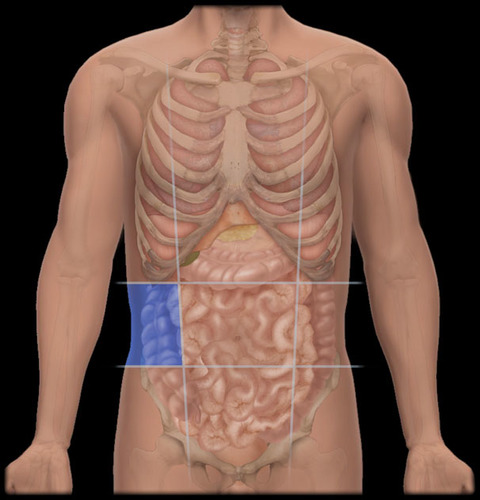

Right lumbar region

<p>Between the right hypochondriac region and the right iliac region, containing parts of the large intestine and right kidney. </p>

Right iliac region

<p>Beneath the right lumbar region, containing the appendix and parts of the large intestine. </p>

Left lumbar region

<p>Left side of the lumbar region, primarily containing parts of the large intestine and left kidney. </p>

Left iliac region

<p>Lower left area of the abdomen, primarily containing parts of the intestines and the left ovary in females. </p>